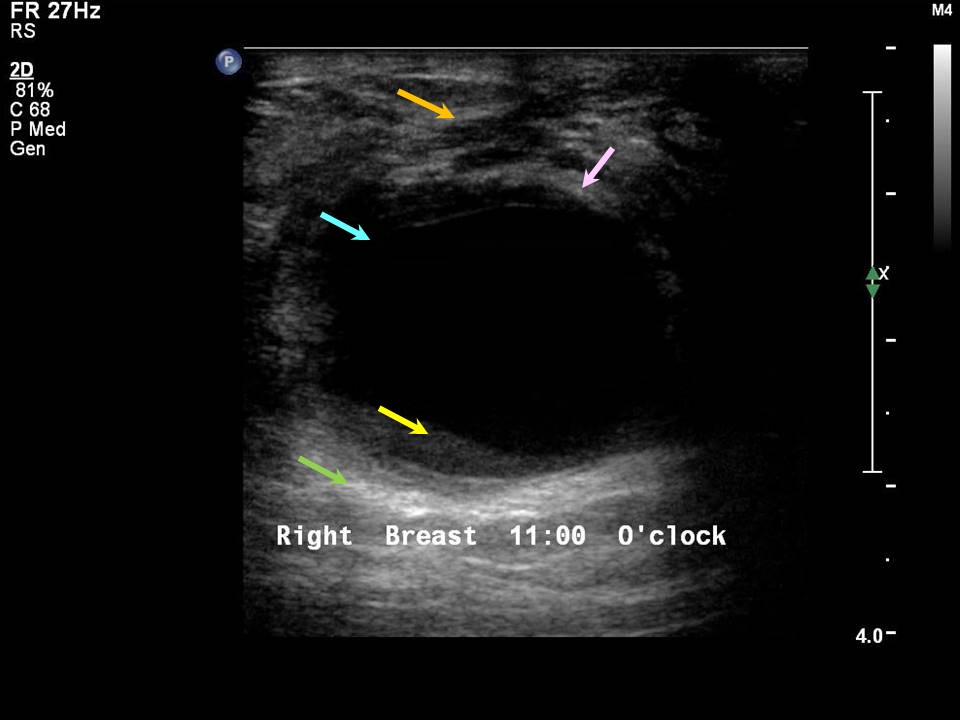

From clinicalimagingscience.org

Epidermoid Cyst in Male Patient Mimicking a Suspicious Breast Mass and Male Cyst In Breast Male breast cancer is a rare cancer that begins as a growth of cells in the breast tissue of men. Men have less breast tissue than women, so it may be easier to discover a lump. Imaging of the male breast generally relies on mammography and ultrasound, with mammography employed as the initial imaging modality of choice and ultrasound when. Male Cyst In Breast.

Epidermoid Cyst in Male Patient Mimicking a Suspicious Breast Mass and Male Cyst In Breast Male breast cancer is a rare cancer that begins as a growth of cells in the breast tissue of men. Men have less breast tissue than women, so it may be easier to discover a lump. The most encountered malignant lesion in the male breast is ductal adenocarcinoma; The most common sign of breast cancer in men is a lump. Male Cyst In Breast.

Epidermoid Cyst in Male Patient Mimicking a Suspicious Breast Mass and Male Cyst In Breast Less often, the lump is located in the upper outer quadrant of the breast. Healthy men typically have predominantly fatty tissue with few ducts and stroma [2], which is distinctly different from women's breasts where ducts, stroma, and. Breast cutaneous cyst is an epidermal inclusion cyst that is considered to be the third most common benign breast mass in. Benign. Male Cyst In Breast.